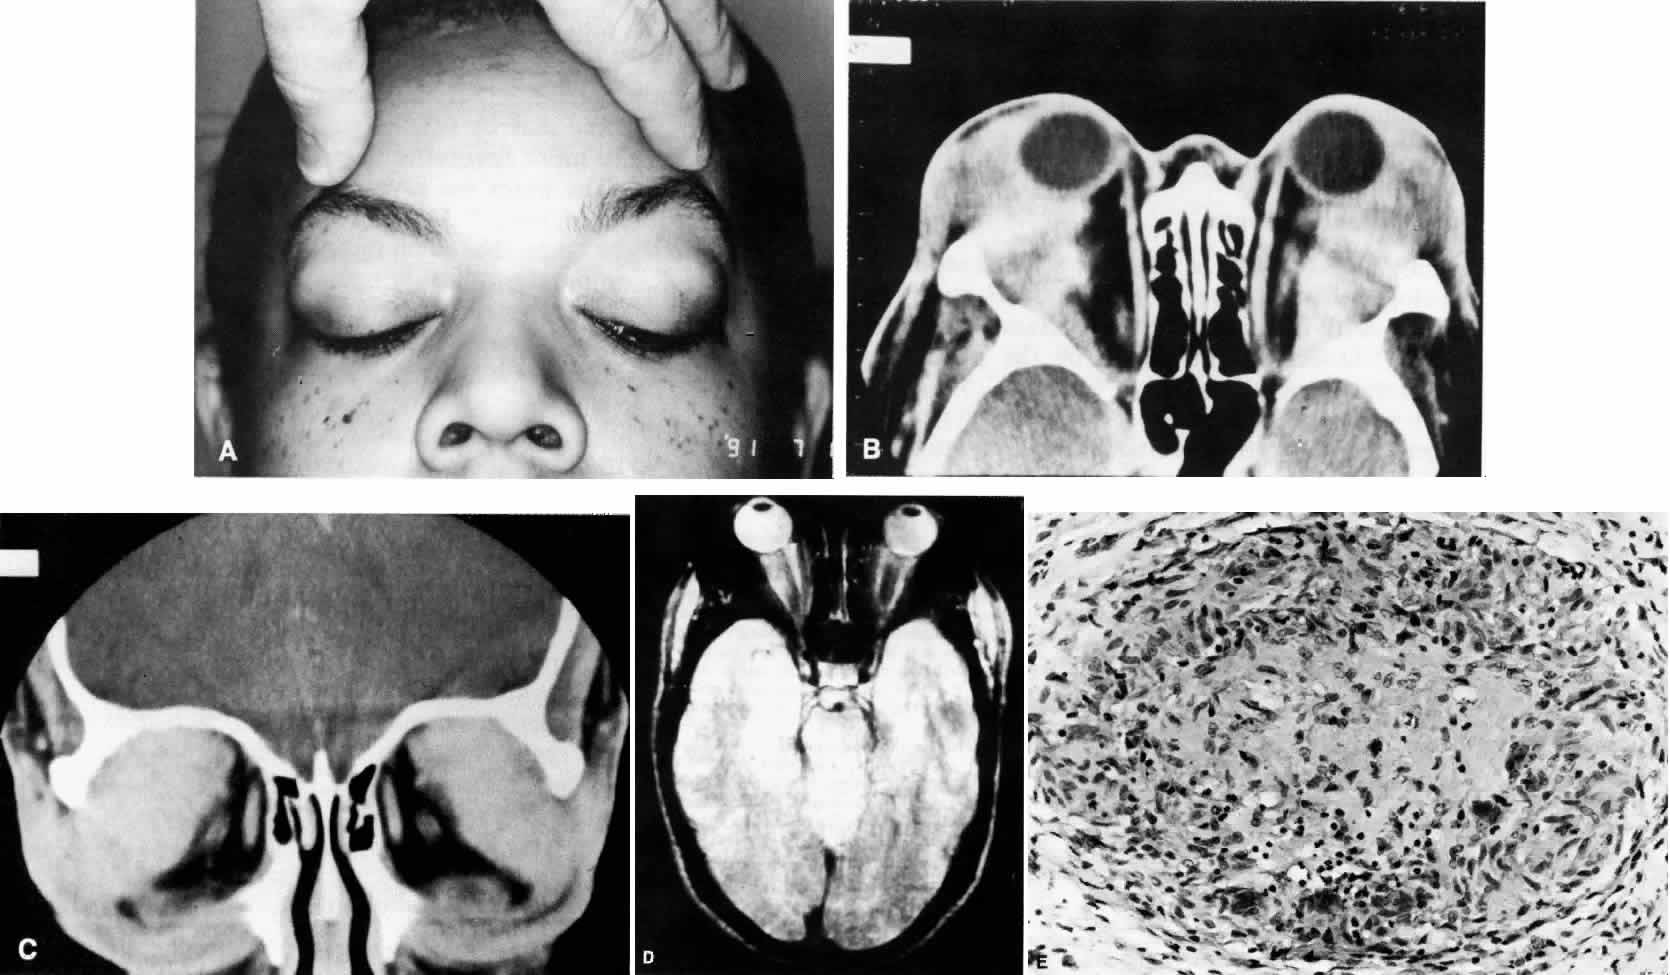

Fig. 1. A. A 36-year-old woman presented with right-sided pain and proptosis occurring over a several-day period. Externally the eye is quiet and does not appear inflamed. The patient had no complaints of diplopia or other visual disturbances. Tissue obtained at biopsy demonstrated idiopathic orbital inflammation. B. Axial CT image from the same patient demonstrates bilateral orbital masses located laterally in the orbits. Note that masses are ill defined and do not appear to have a capsule. The masses are molded to the bony orbital walls without evidence of any bony irregularities. C. Coronal CT image from the patient again shows the presence of bilateral orbital masses apparently involving the lateral rectus muscles.

Fig. 2. A 54-year-old woman presented with acute orbital inflammation demonstrating significant proptosis and inflammatory signs involving the right orbit. In addition to severe pain, the patient had diplopia secondary to orbital edema and inflammation.

Fig. 3. A. A 62-year-old woman presented with diplopia and minimal right-sided proptosis. B. Enlarged lateral rectus muscle is visible subconjunctivally. C. Axial CT image confirms myositis involving the lateral rectus muscle. Note that the muscle as well as its tendon are involved in the inflammatory process in contrast to muscle involvement in thyroid-related orbital disease. D. T1-weighted MRI image demonstrating myositis involving the lateral rectus muscle. In this case the muscle belly is enlarged but the tendon appears relatively unaffected. E. T2 weighted MRI image of orbital myositis showing little difference in appearance of muscle between T1- and T2-weighted images.

Fig. 4. A and B. Gross specimen of old, burned out, involuted granuloma from a patient with idiopathic orbital inflammation. Note lack of vascularity.